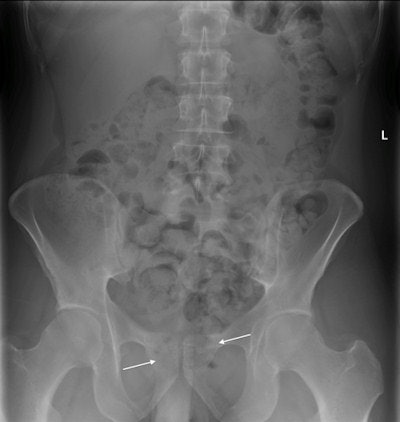

Illegal drugs in the GI tract can cause bowel obstruction or intoxication due to ruptured drug packets in the bowel. Cocaine, heroin, LSD, and other illegal substances in pill form are typically swallowed or passed into the colon per rectum, the authors noted. Heroin and cocaine are mostly wrapped in plastic or condoms, to form 2- to 4-cm packages, which are then swallowed. A mule can often store up to 100 packages in their colon and small intestine. Another method is to put drugs into larger 4- to 6-cm hard plastic containers, which are then placed into the rectum. These containers can hold solid drugs, powder, or pills.

"A large amount of stool in the bowel can be misinterpreted as illegal substances," they noted. "Advised wrapping techniques and a gasless abdomen can make detection of the packages difficult. As only a fraction of the negatively interpreted cases can be verified, it is possible that false-negative interpretations are common."